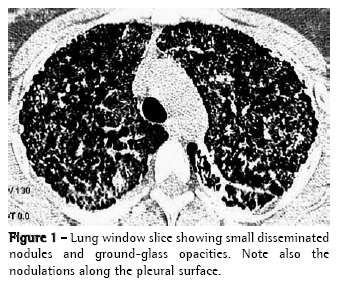

Small parenchymal nodules (Figure 1) were found in seven patients (70%).

Small nodules were identified in 70% of the patients. The small nodules seen on the HRCT scan correspond to dense micronodules (<1 mm), on chest X-rays and are very thin, well-defined, and diffusely spread throughout the parenchyma, making the lungs homogeneously hypotransparent, characterizing the pattern described by some authors as a 'sandstorm' aspect, which is considered typical of the disease. When this pattern is identified in chest X-rays, lung biopsy is needed only in exceptional cases.(1-4) On the HRCT scan, it is often impossible to define the calcium density of the nodules. This is probably due to their small dimensions. When they converge, calcium can be better characterized.